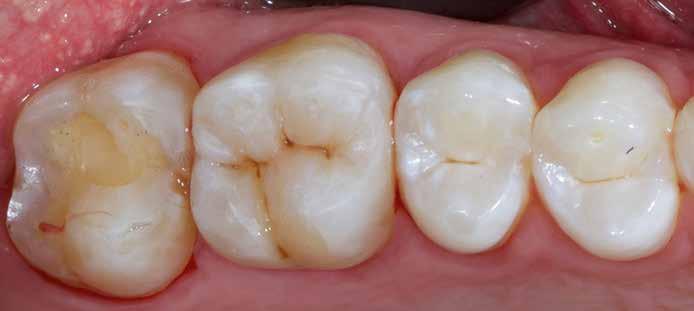

2. eset

Egy 26 éves páciens a jobb felső első molárisának ideiglenes, endodonciai kezelést követő, I. osztályú restaurációjával jelentkezett. Mivel a fogban jelentős mennyiségű dentin és zománc volt jelen, valamint a marginális peremek épek voltak, a páciens tájékoztatása és beleegyezése után a kezelési terv a direkt kompozit restauráció volt (18. ábra). A fog preparálása az 1. esetben leírtak szerint történt (19. ábra).

Végül a szerző az üreget a „Modified Super-Closed Sandwich Approach” [20] technikával állította helyre (amely a klasszikus rezin-módosított üvegionomer zárt-szendvics technika módosított változata), és az okkluzális iránytű módszerét alkalmazta a rágófelszín lezárására (20. ábra).

18. ábra: Felső első moláris ideiglenes töméssel ellátva. – 19. ábra: I. osztályú üreg preparációját követő állapot.

20. ábra: Végleges restauráció.